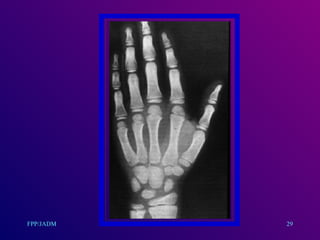

Cont....... evaluación Maduraciónósea : básic a en talla baja. Se identifican el número y tamaño de núcleos de osificación y se comparan con los patrones estandarizados por edad y sexo. Talla esperada : se parte de la talla media familiar más 6.5 cm niños, menos 6.5 cm niñas. 27